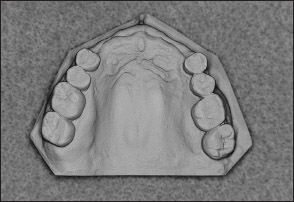

Fig 1-11 Maxillary Kennedy Class I arch.

Fig 1-13 Maxillary Kennedy Class II arch.

Fig 1-15 Maxillary Kennedy Class III arch.

Fig 1-17 Maxillary Kennedy Class IV arch.